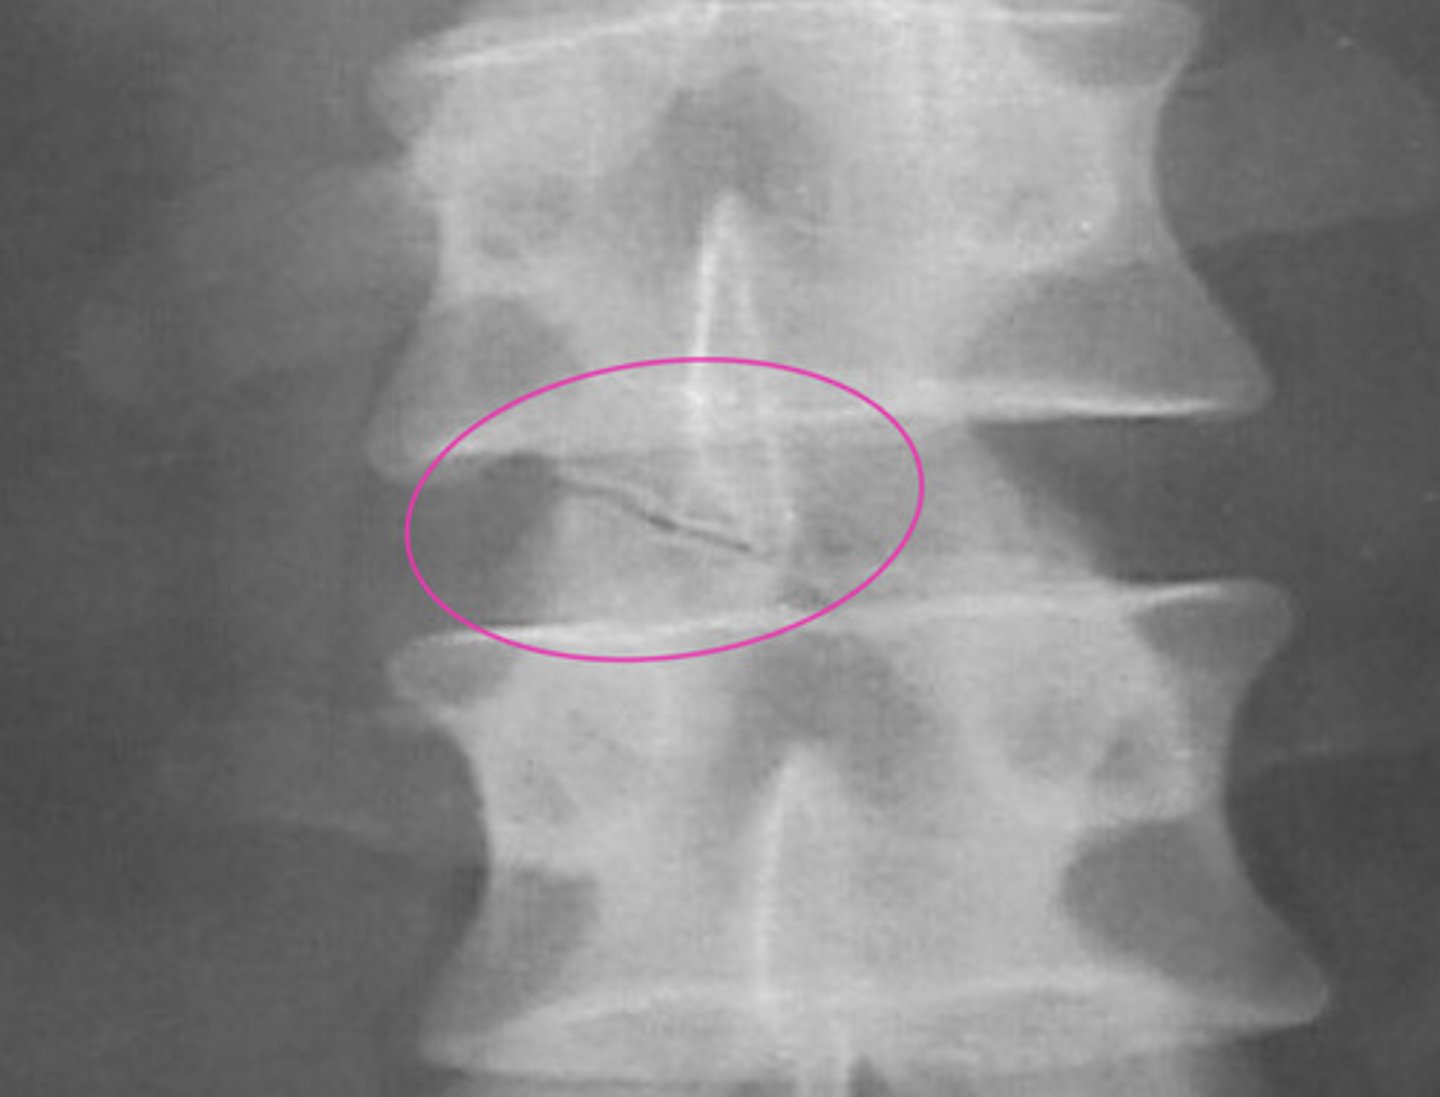

Hahn Vascular Cleft/Groove/Canal

Embryonic vascular channel = vertebral vascular foramina (Hahn Canal)

Do not mistake for a fracture

NO clinical significance

What does the Hahn Canal transmit?

— basivertebral veins

— intraosseous nutrient arteries

— basivertebral nerve